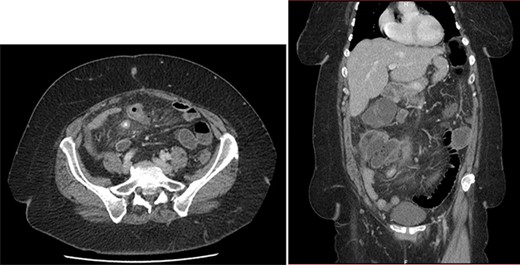

Abdominal CT showed signs of non-complicated appendicitis: intra-appendicular liquid, microstercoliths and peri-appendicular inflammation (Fig. 1).

Emergency CT: acute appendicitis with: intra-appendicular liquid, microstercoliths and peri-appendicular inflammation.